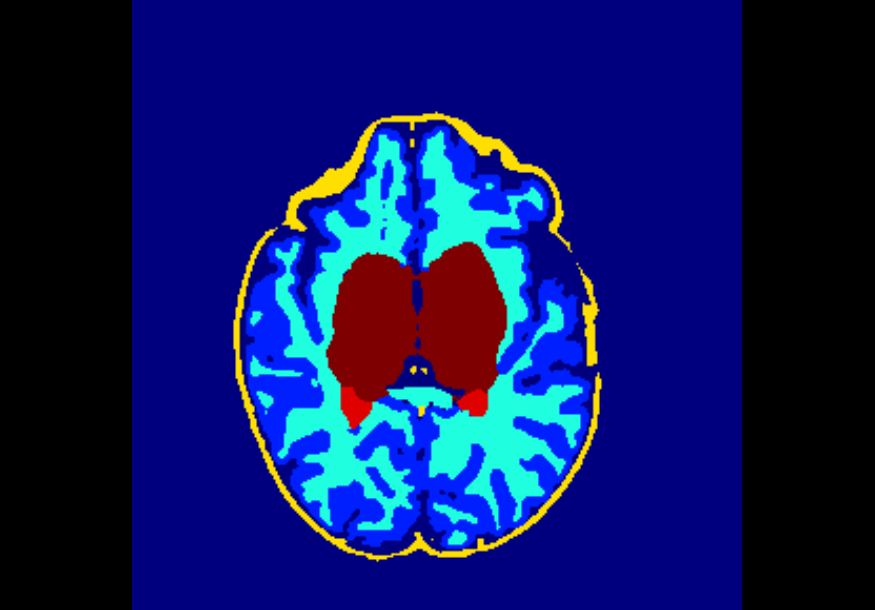

The dataset consisted of 70 3D T2-weighted brain MRI scans publicly available from the dHCP neonatal cohort. The segmentation maps had 10 classes, corresponding to: zero-pixel background, cerebrospinal fluid (CSF), cortical grey matter (cGM), white matter (WM), background bordering brain tissues, ventricles, cerebellum, deep grey matter (dGM), brainstem, and hippocampus. The scans covered an age range of 24.3-42.2 weeks. The data was available in NIfTI format; Figure 1 shows an example scan and corresponding tissue labels. We carried out a pre-processing step where each scan was independently normalised to zero-mean and unit-variance.

Finally, Table 4 shows that the model trained on data injected with different degrees of both Gaussian and salt-and-pepper noise (gaus01, gaus03, gaus04 with = 1, 3, 4 ; snp01, snp05, snp10 with prob = 0.01, 0.05, 0.10) achieves the best overall robustness across the 16 versions of the test set, where even the heaviest filtered images had very few segmentation inaccuracies. For instance, this model demonstrated high levels of robustness on all 10 classes for noise-free data, on data injected with a previously unseen degree of salt-and-pepper noise (e.g. DSCs of 88%-99% on snp20), as well as on data with a previously unseen degree of Gaussian noise (e.g. DSCs of 72%-98% on gaus05). To illustrate, Figure 5 shows examples of the predicted segmentation of the model on the heaviest transformed images of the three filter categories used in these experiments. From the figure it is clear that the model achieved excellent mapping of the brain tissue regions. This shows a tremendous improvement from the baseline model which was trained using a conventional, noise-free approach and thus failed severely on the heavily corrupted images (e.g. DSCs of 0% for all 10 classes on snp20, see Table 2).